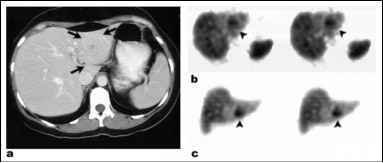

FNH

hot on sulfur colloid

retains eovist on delayed MR scan